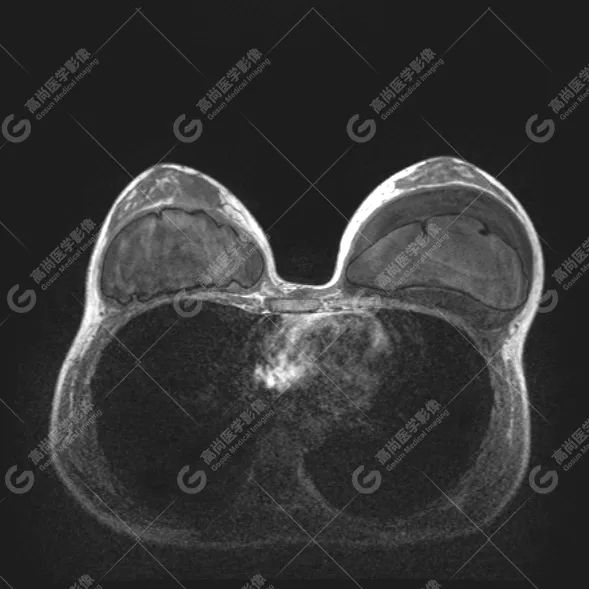

病例 4:乳腺注射物部分取出术后,后硅胶假体植入术后 3 年余

双侧假体包膜不光整,包膜下可见多发线样低信号影,左侧假体内可见「面条征」——双侧假体内包膜破裂(部分破裂)